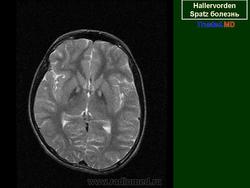

ГМ. Галлервордена - Шпатца болезнь. +

Галлервордена - Шпатца болезнь

Болезнь Галлервордена - Шпатца - наследственное заболевание экстрапирамидной системы, связанная с нарушением обмена железа и липидов и повреждением бледного шара и черной субстанции. Тип наследования аутосомно-рецессивный. При патоморфологическом исследовании характерным признаком является гиперпигментация бледного шара и черной субстанции. Обнаруживается пигментация коры полушарий большого мозга и таламуса. Пигмент находится внутри невронов и глиальных клеток, расположенных около сосудов; содержит железо (вместе с тем каких-либо нарушений обмена железа в организме не обнаружено). Наблюдаются утолщение и фрагментация аксонцилиндров в пораженных областях. Постепенно наступает дегенерация невронов коры полушарий большого мозга и мозжечка. Характеризуются нарастающей экстрапирамидной ригидностью, гиперкинезами (атетоз, торсионная дистония), затем развивается акинетико-ригидный синдром, пирамидная микросимптоматика, снижение интеллекта. Течение медленно прогрессирующее на протяжении 10 - 20 лет.

"Глаз тигра"-наглядно и красиво.